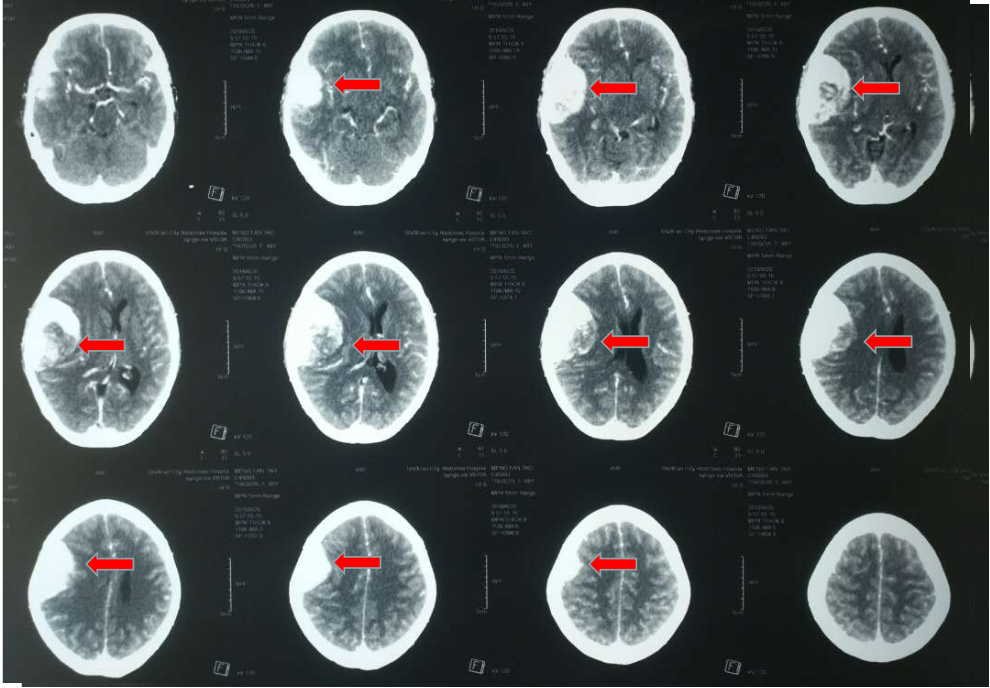

图-:2010年9月7日头颅ct整合.png

头部ct提示脑出血,中线偏移12mm,大脑

术前颅脑ct显示